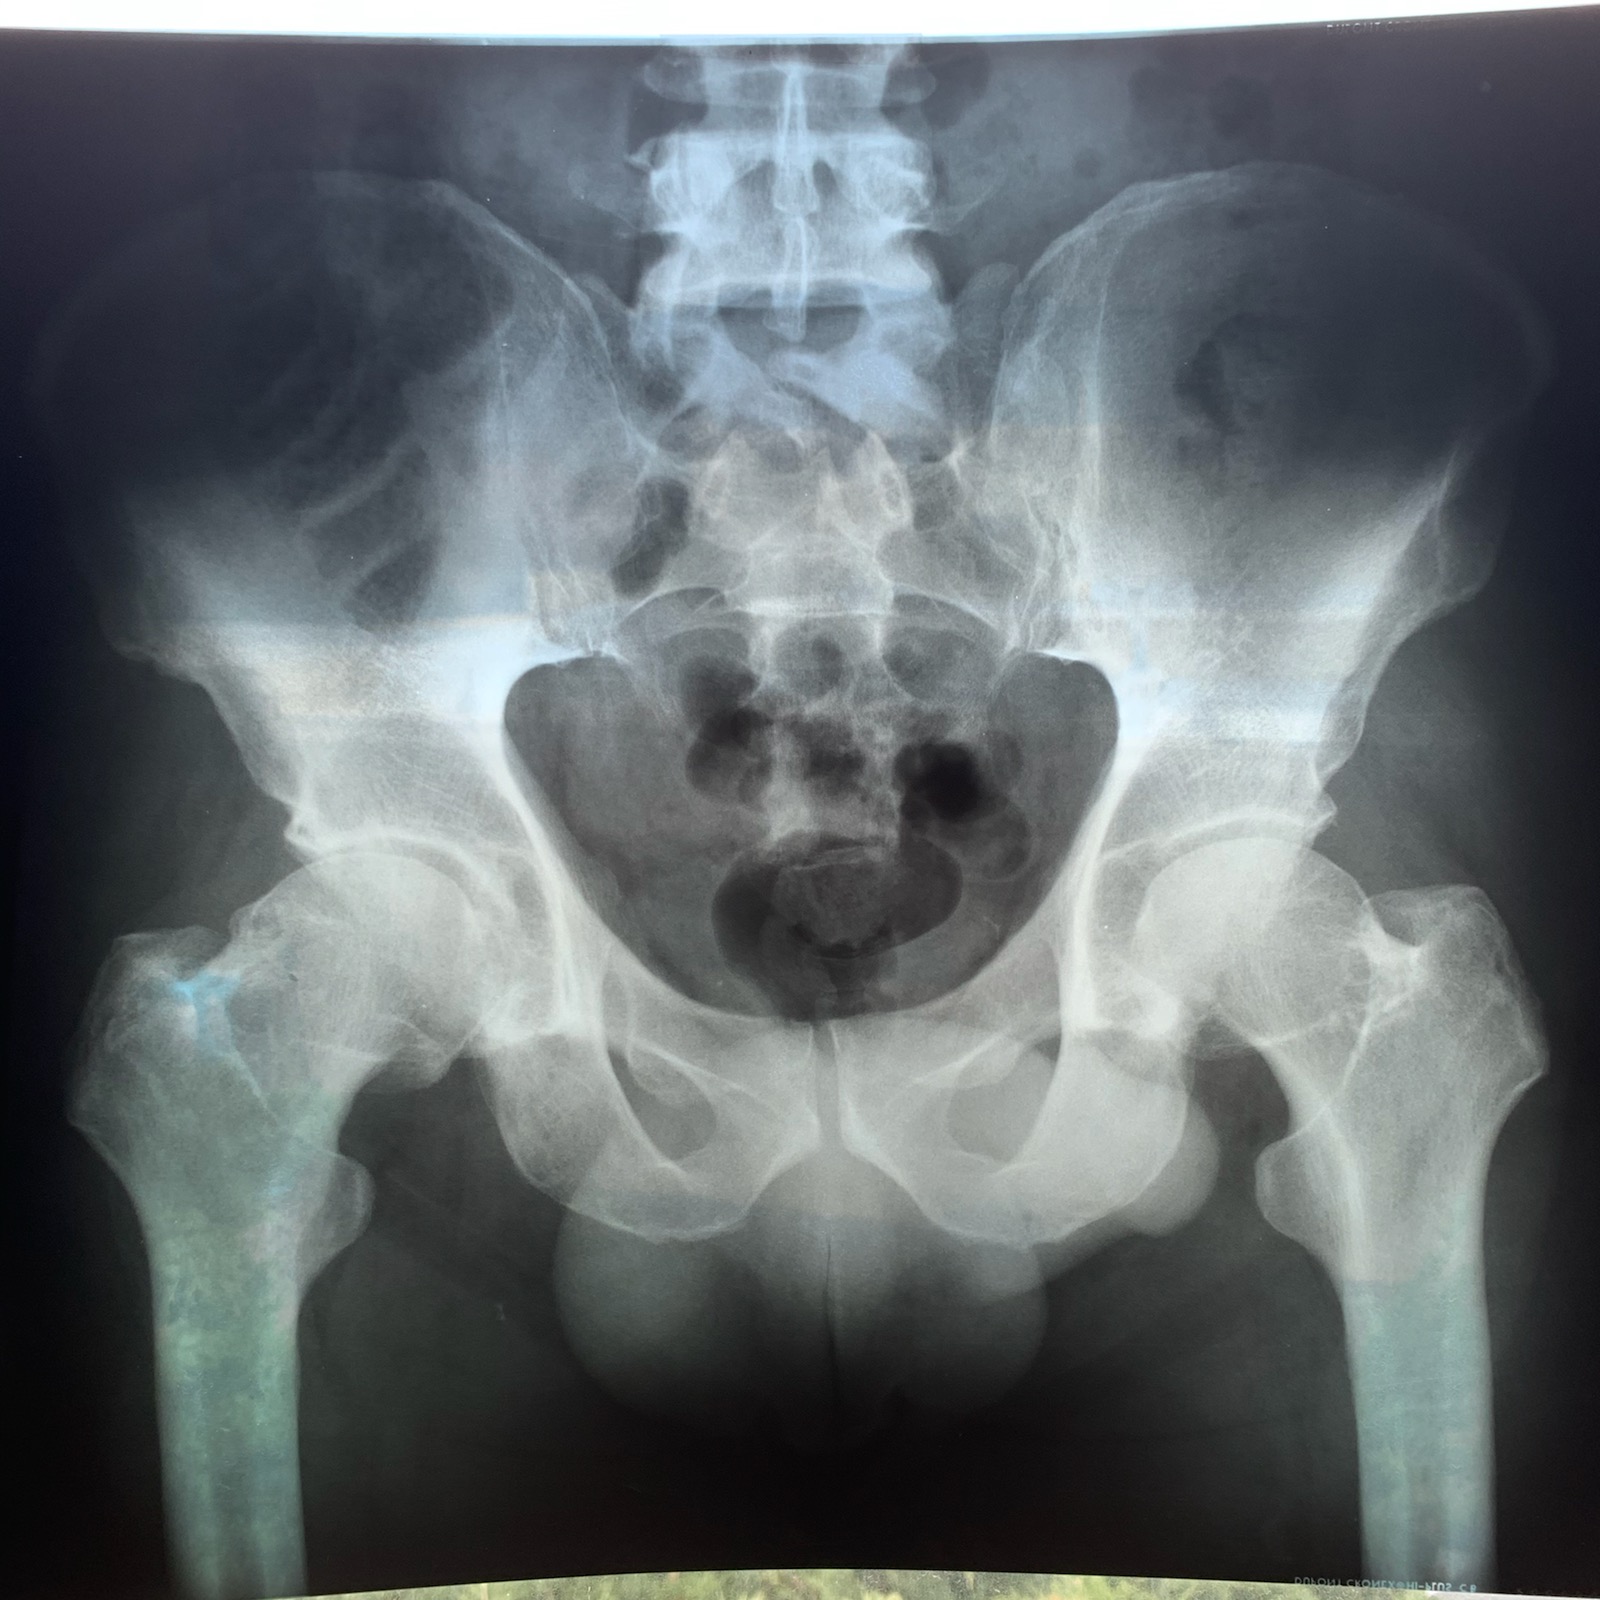

Dr. Harper performs a brief Hip & L-3 exam and demonstrates 4 different injections to support a chronic longstanding degenerative hip as shown on X-Ray (included)